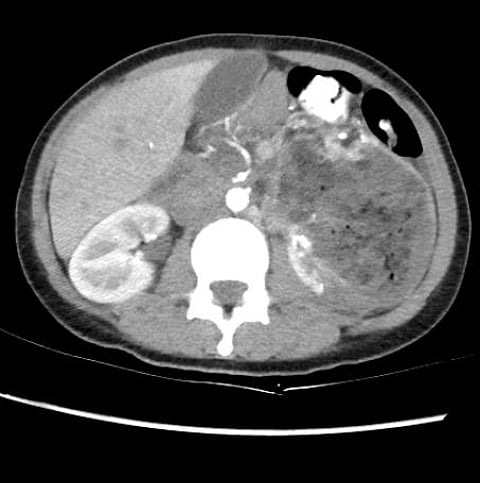

أنقذ فريق طبي متخصص في وحدة الأشعة التداخلية بمجمع الملك فيصل الطبي عضو تجمع الطائف الصحي، حياة شابة تبلغ من العمر عشرين عامًا كانت تواجه خطرًا محدقًا؛ بسبب ورم شحمي وعائي عظمي كبير في الكلية اليسرى، كشفه التشخيص الدقيق عبر الأشعة المقطعية؛ حيث كان الورم يهدد بنزيف حاد قد يعرّض حياتها للخطر.

وفي مواجهة هذا التحدي، استخدم الطاقم الطبي تقنية القسطرة والأشعة التداخلية لإصمام الأوعية الدموية المغذية للورم؛ مما أتاح إجراء العملية دون اللجوء إلى التدخلات الجراحية الكبيرة.